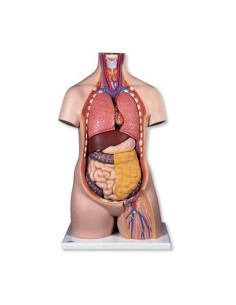

Scopri il Mondo dell’Anatomia con Modelli anatomici di Precisione

Modelli Anatomici Dettagliati per Ogni Necessità

Dal cranio in 22 parti con incastri magnetici ai modelli di colonna vertebrale, da quelli di articolazioni a quelli di cuore, ogni pezzo della nostra collezione è progettato per un’immersione totale nello studio dell’anatomia umana. I nostri modelli, realizzati tramite scansioni di ossa vere, garantiscono un’esperienza tattile autentica e una fedeltà di peso quasi identica agli originali.

Strumenti Didattici Innovativi per l’Educazione e la Pratica Medica

Essenziali per studenti e professionisti, i nostri modelli anatomici sono strumenti didattici che permettono di osservare le strutture anatomiche con precisione, eliminando la necessità di dissezioni o studi invasivi. Sono inoltre utili per spiegare ai pazienti le patologie, rendendo la comunicazione più efficace e risparmiando tempo prezioso.